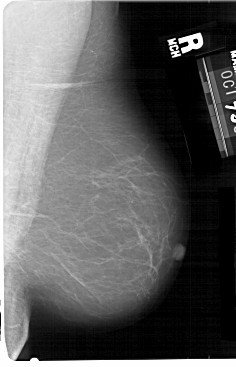

A_1476_1.RIGHT_CC

RIGHT_CC LINES 5491 PIXELS_PER_LINE 3421 BITS_PER_PIXEL 12 RESOLUTION 43.5 NON_OVERLAY